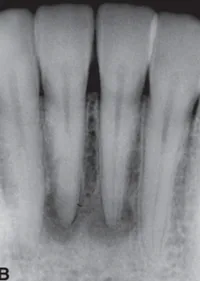

Your patient is a 43-year-old female. Radiographs reveal well-defined, round radiolucencies at the apices of all mandibular incisors. The teeth reveal no caries or fracture and they test vital and are asymptomatic. What is the likely diagnosis?

Periapical cemento-osseous dysplasia